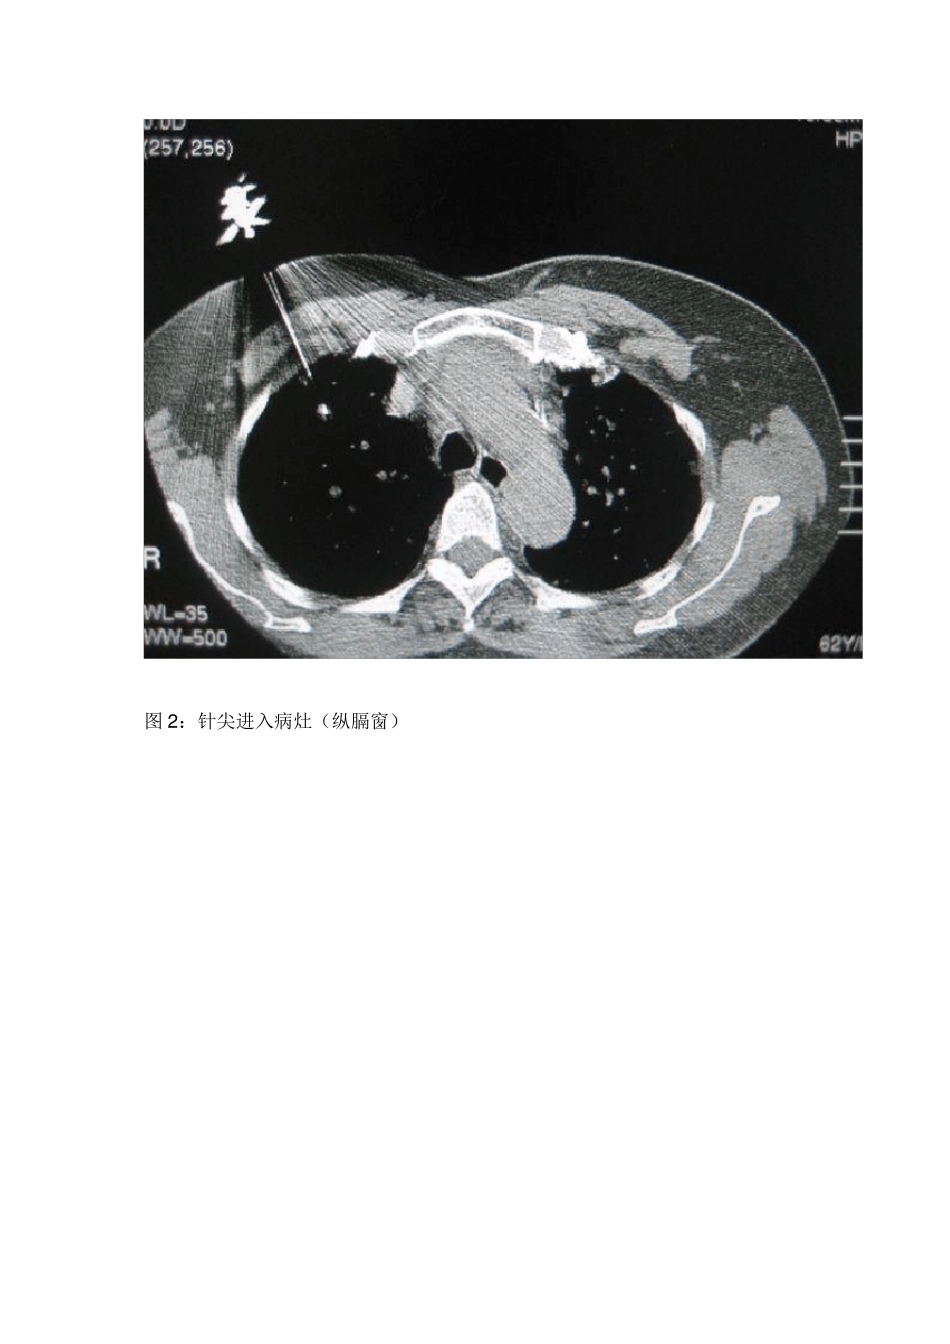

CT引导下经皮肺穿刺的几点心得 CT引导下经皮肺穿刺是肺部疾病的一种重要的诊断方法,当然也很老了,是指在CT扫描定位协助下,通过体外的穿刺针或活检枪对肺内病灶进行负压吸引或切割活检,取得病灶组织后送检来进行诊断和鉴别诊断的一种手段。 具体的操作步骤:在CT光标指示下,以记号笔标记出穿刺点,常规消毒、铺巾,局部麻醉后,穿刺针进入皮下后行CT扫描,直观地确定进针角度和病灶的关系后,按预定的进针角度和深度穿刺进针至靶点,再行靶层面 CT扫描,证实针尖位于病灶内,即负压吸引或活检枪击发取材。抽吸活检时抽吸针保持负压拨出,将内容物推到玻片上;组织针取出有形组织条送入 10%福尔马林液内固定。术后常规胸部CT扫描,观察有无气胸等并发症发生,如无不适,嘱患者回病房静卧 1-2 小时。 CT引导下经皮肺穿刺常见的并发症有气胸、肺出血、少量咯血和胸膜腔出血等。最常见的术后并发症主要为气胸和肺内出血,文献报告气胸发生率为 9%~44%,多在10%左右,大多是少量气胸,无需特殊处理休息吸氧后短时间可自行吸收,需做胸腔闭式引流的病人仅占 1.6%~14.3% ;肺内出血 1~3 日可自行吸收,少数病人有痰中带血;大咯血和胸膜腔出血的发生率较低。并发症的发生与操作者的熟练程度、进针次数、穿刺针与穿刺点胸膜切线位的角度及患者肺的质量如有无肺气肿等因素有关。 心得一:首先如何预防 CT引导下经皮肺穿刺的并发症? 1)首先术前进行患者教育,配合医生的操作,保持相同的呼吸状态。 2)正确地评估,要确定好穿刺层面和进针点,以及进针深度、角度和呼吸对穿刺的影响。穿刺点到病变距离最短,以垂直方向或水平方向为佳。尽量避开叶间胸膜、肺大疱及 CT 下能显示的粗大血管影或肺纹理等。 3)麻醉针不宜穿刺太深,若刺破胸膜,会增加气胸的概率。 4)穿刺胸膜时,病人应在平静呼气后屏气状态下进行,动作迅速地刺入靶点,尽量缩短穿刺经过胸膜的时间。 5)穿到细胞或组织后,应在呼气末负压迅速拔出穿刺针。 心得二:如何穿到肿瘤组织内。 当然,常规的、较大的、贴近胸膜的病灶是不用说的,要讲的是小病灶、骨组织后的难以取得的病灶或靠近大血管病灶和肺气肿患者。 1)小病灶 图1:56 岁女性患者,病灶太小,不到1cm 。上海某三甲医院无法找到病理。 针对图1 患者,病灶太小,一定要镇静,患者的任何呼吸都会影响病灶的位置,因此必须告诉患者CT 扫描时保持同样的呼吸状态(呼气末),当然进针时也必...